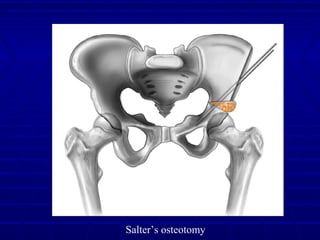

Salter OsteotomySalter Osteotomy

Salter’s OsteotomySalter’s Osteotomy

Redirects the entire acetabulumRedirects the entire acetabulum

Roof “covers” the femoral head anteriorlyRoof “covers” the femoral head anteriorly

and superiorlyand superiorly

Hinge at pubic symphysisHinge at pubic symphysis

Pre-requisitesPre-requisites

Congrous Concentric reductionCongrous Concentric reduction

No ContracturesNo Contractures

Salter’s osteotomy